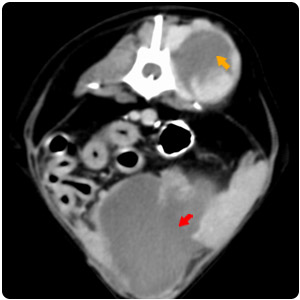

| 背部腫塊、膽囊結石 |

胸腔積液(黃)、心包囊積液(紅)、

肝腫大伴有不均質影像(紫)、腹水(綠)、

脾腫塊(藍) |